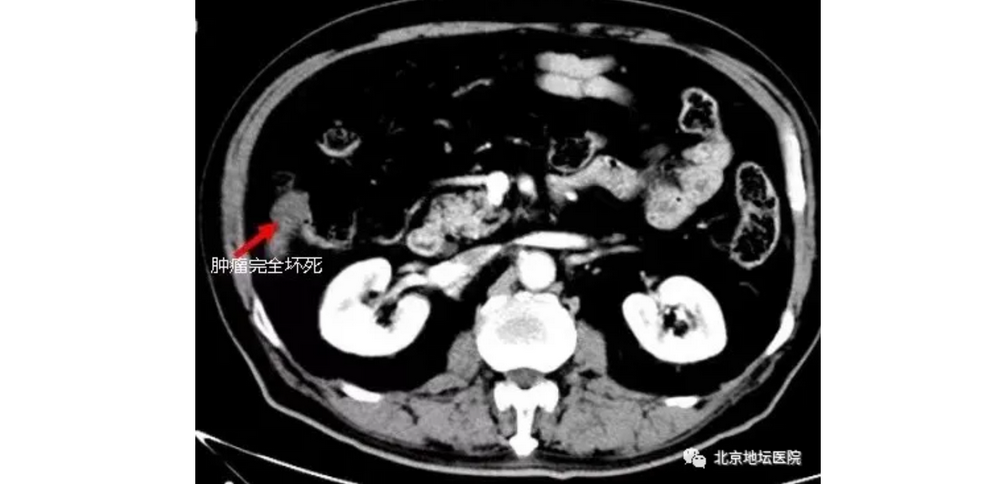

最终,在射频、酒精消融这两种微创手术的“强强联合”,加上局部水隔离的“神助攻”下,王大爷的肝癌得到了根治。经过半年的随访,也没有复发的迹象。

消融手术目前已经成为了除了外科手术外,又一种根除癌症病灶的根治性手段。

只不过肿瘤还在患者体内,但其实那已经是一个完全坏死的病灶,对人身体健康不会再构成任何威胁。